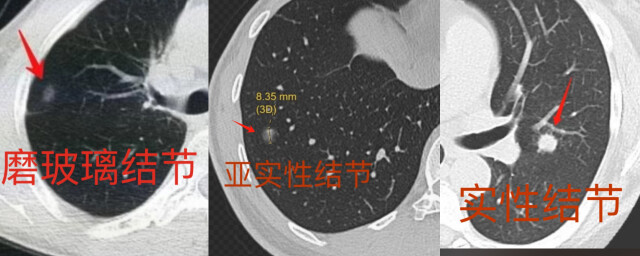

肺结节是指直径小于3厘米的圆形或类圆形肺部阴影,肺结节在CT上可以表现为实性结节、亚实性结节(包括部分实性和纯磨玻璃样结节)等多种类型。